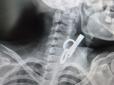

Проковтнула, щоб не пустити родичів у хату: На Тернопільщині лікарі витягнули зі стравоходу 40-річної пацієнтки ключ від дверей

У селищі Гусятин на Тернопільщині лікарі врятували життя 40-річній пацієнтці. З її стравоходу витягнули дверний ключ. Вона його проковтнула, щоб не пускати родичів у хату. До лікарні пацієнтка потрапила в шоковому стані. Медики встигли діагностували пр...